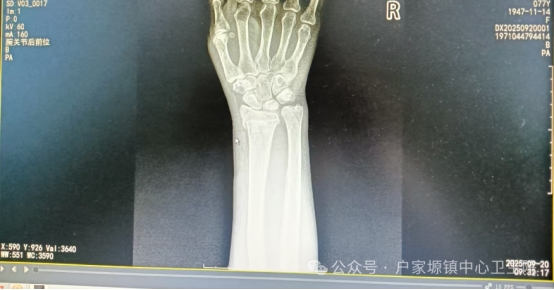

此前,一名10岁儿童玩耍时不慎摔倒导致肱骨髁上骨折,家长焦急万分地将孩子送至卫生院。骨科团队迅速响应,仅用20分钟便完成手法复位,随后采用夹板固定保护。复查时,孩子骨折愈合良好,肘关节活动自如。类似的案例在卫生院屡见不鲜——从老年人不慎摔倒导致的手腕骨折,到青壮年劳作时意外造成的脚踝骨折,医生们凭借过硬技术,帮助患者免去手术之苦,缩短恢复周期,减轻经济负担。

作为服务乡镇群众的“健康守门人”,户家塬镇中心卫生院始终聚焦基层常见骨折病症,组建专业骨科诊疗团队,团队成员均具备多年临床经验,熟练掌握桡骨远端骨折、儿童肱骨髁上骨折、踝关节骨折等常见骨折的手法复位技巧。诊疗中,医生会结合患者年龄、骨折类型、移位情况精准评估,通过“摸、接、端、提、按、摩、推、拿”等传统手法,配合现代影像学检查辅助定位,在避免手术创伤的同时,实现骨折断端的精准复位,最大程度保留关节功能。